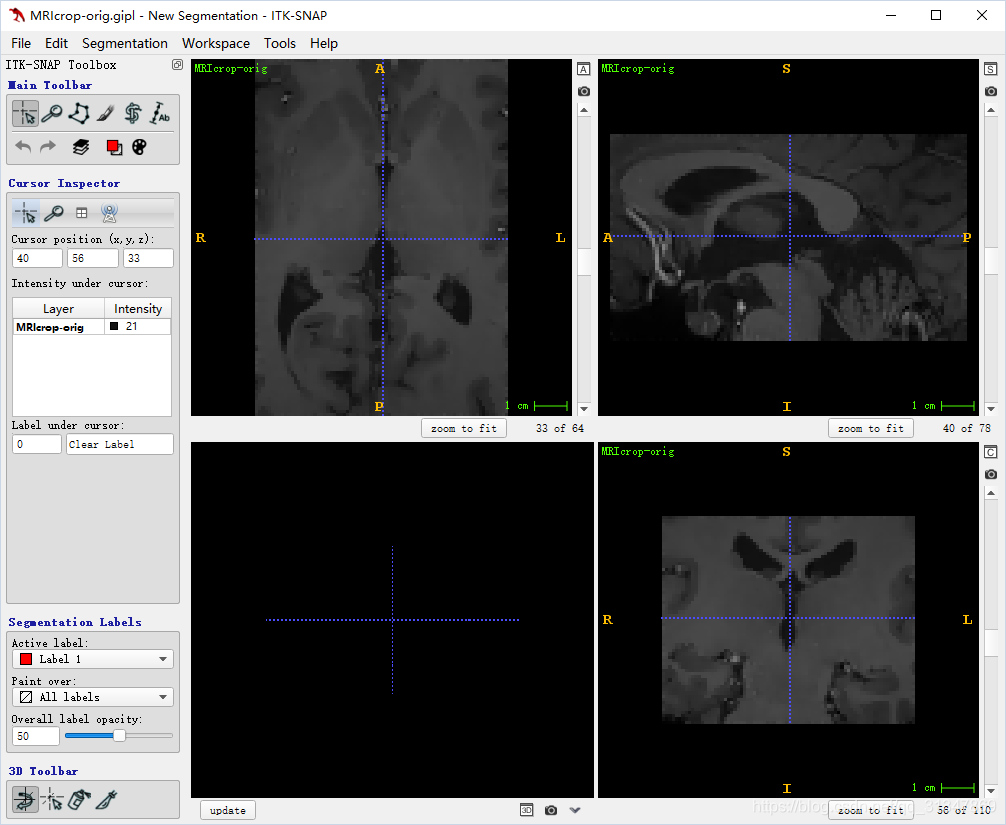

使用界面

左下方视图显示了当前的 3D 视角,其余三个视图是三个正交的切片图(轴向,冠,矢)

四块视图窗口下的蓝色按钮用来单独对当前视图进行一些操作

左边是控制面板

顶部的 menu 用于加载和保存图像,以及一些基本设置

其余按键会根据当前操作的模式出现/消失

- ITK-SNAP Toolbox:选择不同的操作模式

- Cursor Inspector:显示目前光标选择的位置以及灰度值

- Segmentation Labels:选择标签

- 3D Toolbar:额外工具

三个切片窗口分别显示了:

- 轴向面

- 冠状面

- 矢状面

右侧有一个滚动条,滚动条下方是切片计数器,左边的数字是当前的切片索引,右边的数字是该方向上的切片总数